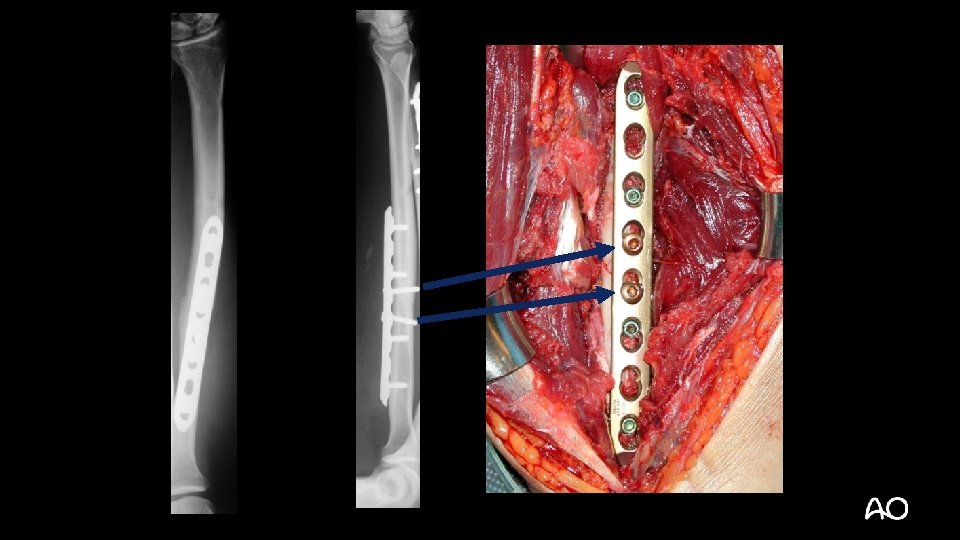

• 32 -year-old man • Motorcycle accident • Isolated injury • Open

2 R 2 B 2 2 U 2 B 2

• 32 -year-old man • How would you expect these fractures to heal?

6 months Absolute stability = direct healing without callus Bridge plate = Relative stability = indirect healing with callus